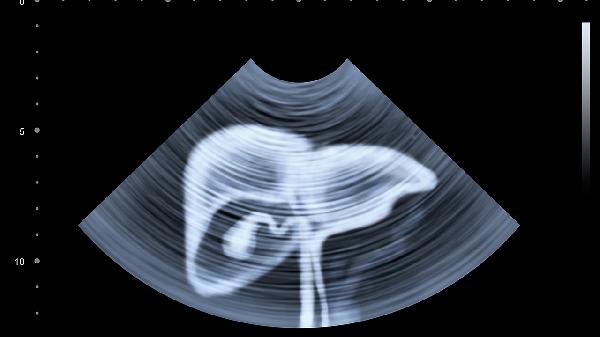

2、定期监测肝功能是预防复发的重要手段。通过检测肝功能指标和病毒载量,可以及时发现异常。建议每6个月进行一次肝功能检查和病毒载量检测,确保病情稳定。